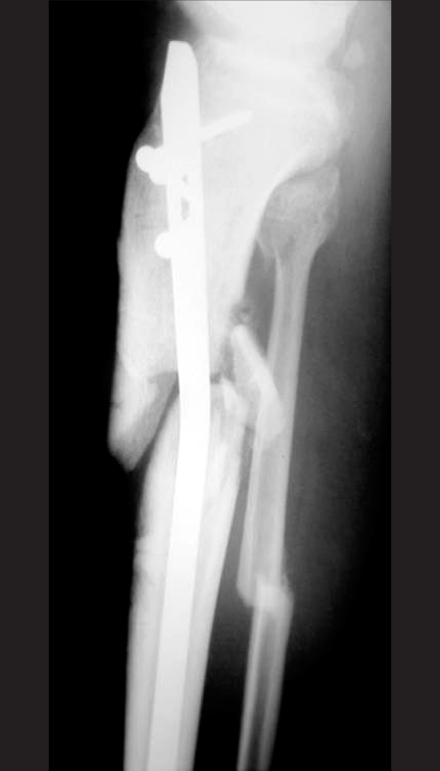

Fig. 6

Postoperative radiographs of this proximal tibial shaft fracture show good alignment after locked tibial nailing using the lateral starting point in line with the lateral intercondylar eminence and more proximal and posterior starting point.

Fig. 6 Postoperative radiographs of this proximal tibial shaft fracture show good alignment after locked tibial nailing using the lateral starting point in line with the lateral intercondylar eminence and more proximal and posterior starting point.